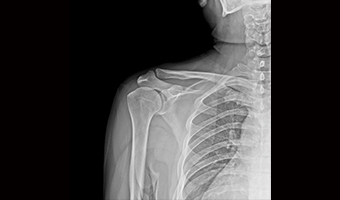

Uygulama Görüntüleri

Tam Boyut